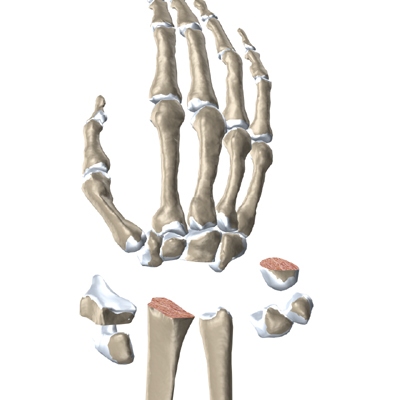

The wrist is made up of eight separate small bones, called the . The carpal bones connect the two bones of the forearm, the radius and the ulna, to the bones of the hand. The metacarpal bones are the long bones that lie mostly underneath the palm. The metacarpals are in turn attached to the phalanges (the bones in the fingers and thumb).

One reason that the wrist is so complex is that every small bone forms a joint with the bone next to it. This means many small joints make up the wrist joint. Ligaments connect all the small bones to each other, and to the radius, ulna, and metacarpal bones.

Articular cartilage is the smooth, rubbery material that covers the bone surfaces in most joints. It protects the bone ends from friction when they rub together as the joint moves. Articular cartilage also acts sort of like a shock absorber. Damage to the articular cartilage eventually leads to degenerative arthritis.